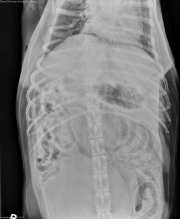

This week’s case is a 12-year-old male neutered Labrador Retriever who is straining to urinate and defecate. Hypercalcemia was noted on serum biochemistry. Where is the abnormality?

There is a large, lobular, soft tissue opacity mass in the caudal retroperitoneal space. The colon is displaced ventrally, and is distended with fecal material. The bladder is enlarged and cranially displaced. The peritoneal detail is good. The liver, spleen, and kidneys are normal in size and shape. No abnormalities are noted in the stomach or small intestine. There is spondylosis deformans at the lumbosacral space.

Sublumbar lymphadenopathy – metastatic disease from pelvic neoplasia, lymphoma

Metastatic anal sac adenocarcinoma